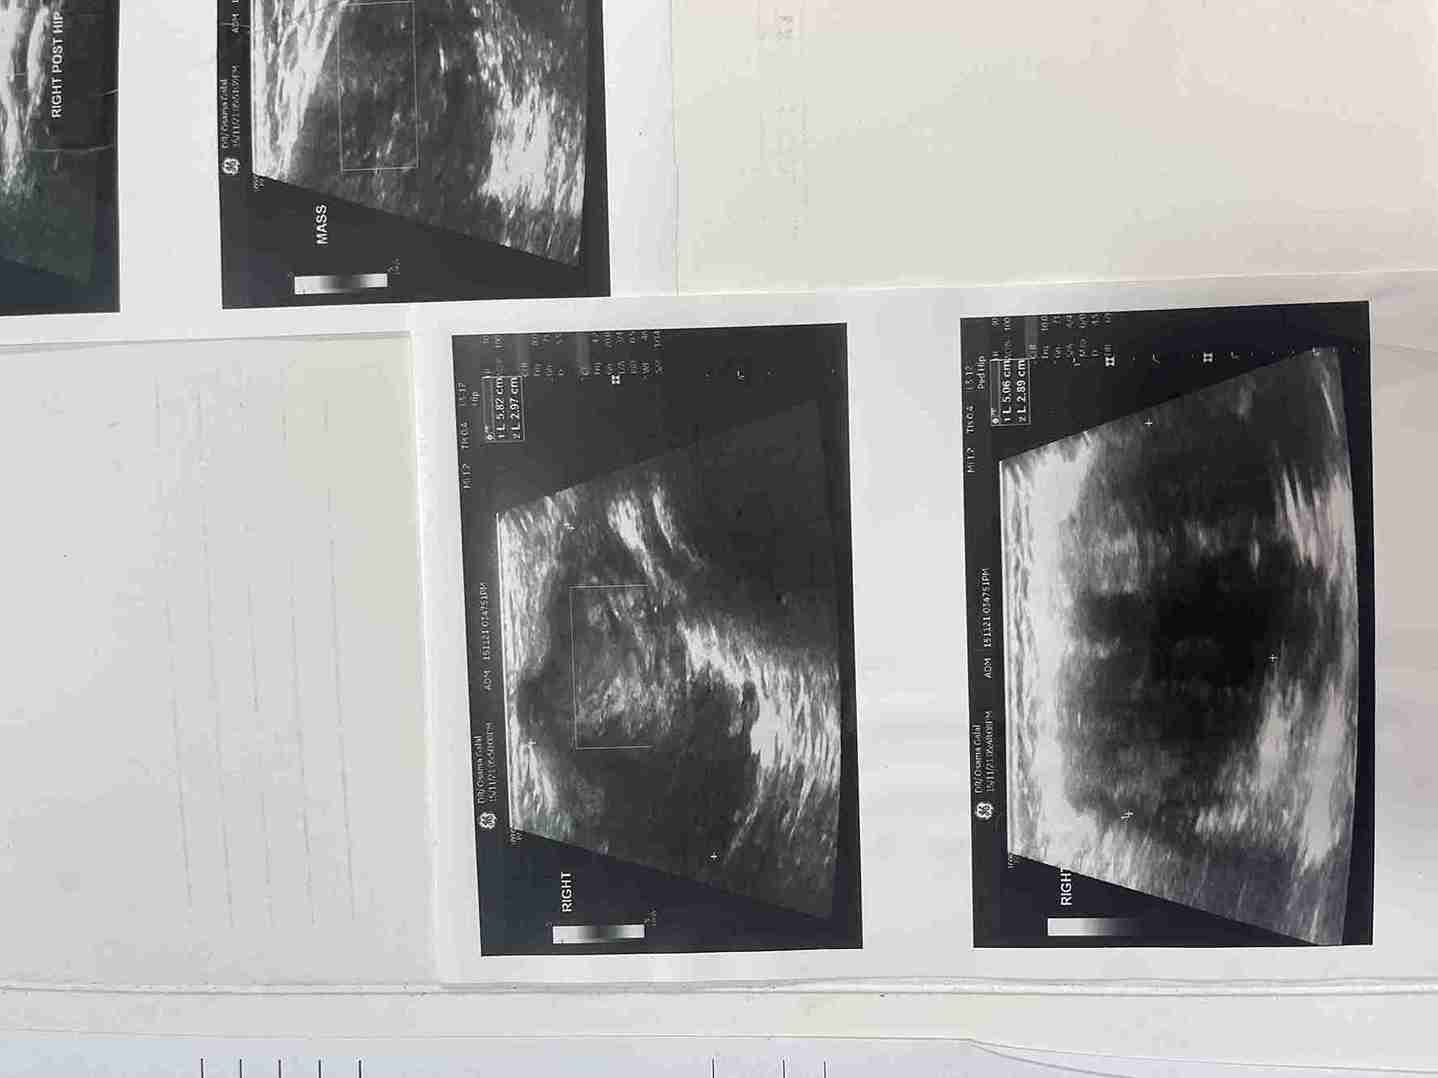

تم في هذه الحالة استئصال ورم حميد نادر (شوانوما) كان موجوداً على غلاف العصب الوركي (عرق النسا) الأيمن لطفلة تبلغ من العمر 5 سنوات ونصف. الورم كان يضغط على العصب مسبباً ألماً في منطقة الفخذ والأرداف. تمت الجراحة بنجاح تام مع الحفاظ الكامل على سلامة ووظيفة العصب.

• شكوى الطفلة من ألم متكرر في منطقة الفخذ والأرداف.

• وجود كتلة محسوسة يمكن اكتشافها بالفحص.